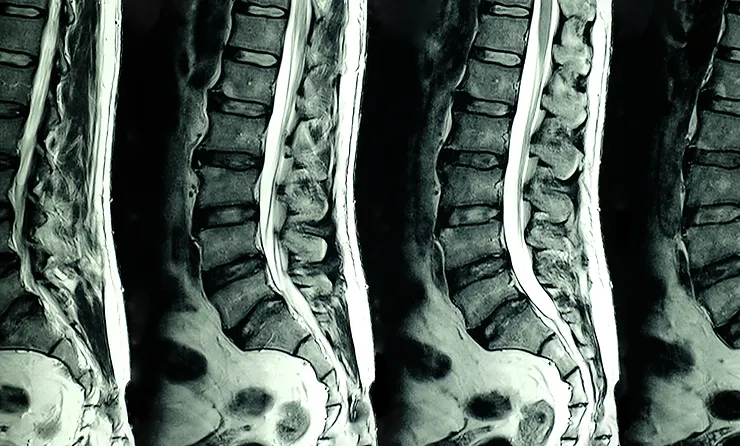

When I first received my MRI report and was diagnosed with a herniated disc and degeneration, I felt completely lost and overwhelmed. The pain, the uncertainty, and the sheer amount of information left me feeling unsure of what to do…